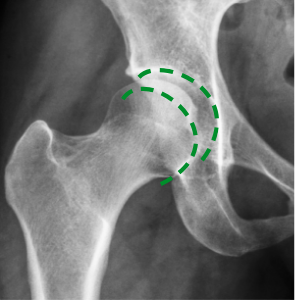

Na zdjęciu po lewo (wykonanym przed kuracją) widać niedobór mazi stawowej, który powoduje ścieranie się kości. Na zdjęciu po prawej stronie dzięki kuracji kości poruszają się płynnie i bezboleśnie. Struktura mazi stawowej się odbudowała – odzyskała właściwości poślizgowe.

Prof. Zygler udowodnił (o czym świadczą zdjęcia rentgenowskie i USG), że jego formuła antyartretyczna wpływa na regenerację stawu na trzech głównych płaszczyznach:

usuwa obrzęki stawów – dzięki likwidacji stanów zapalnych,

zmniejsza tarcie w stawach – dzięki zwiększonej produkcji doskonałej jakości cieczy synowialnej,

permanentnie eliminuje ból – dzięki regeneracji chrząstki stawowej.

Już po 4–5 tygodniach kuracji Zyglera chrząstka stawowa zmieni się z cienkiej i popękanej w grubą i sprężystą. Dzięki temu zmniejszy się tarcie w stawach, a każdy ruch będziesz wykonywać pewnie i lekko.